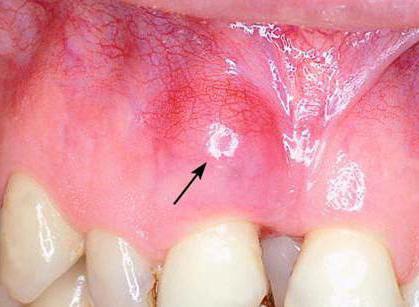

На вид нагноение в мягких тканях может быть разным. Иногда возникает припухлость на десне, охватывающая незначительный участок. Через некоторое время в этой области появляется свищ, наполненный мутным веществом. Это гной. В период истончения тканей, свищ прорывает и его содержимое выходит наружу.

- Возникает белый свищ, заполненный гнойным содержимым.

Помимо вышеперечисленных симптомов, нарыв сопровождается появлением свища. После того, как он прорвет, гной при нажатии на десну или самопроизвольно попадает в ротовую полость. В случаях, когда новообразование расположено слишком глубоко, его содержимое не может выйти наружу. Тогда образуются гранулемы или кисты.